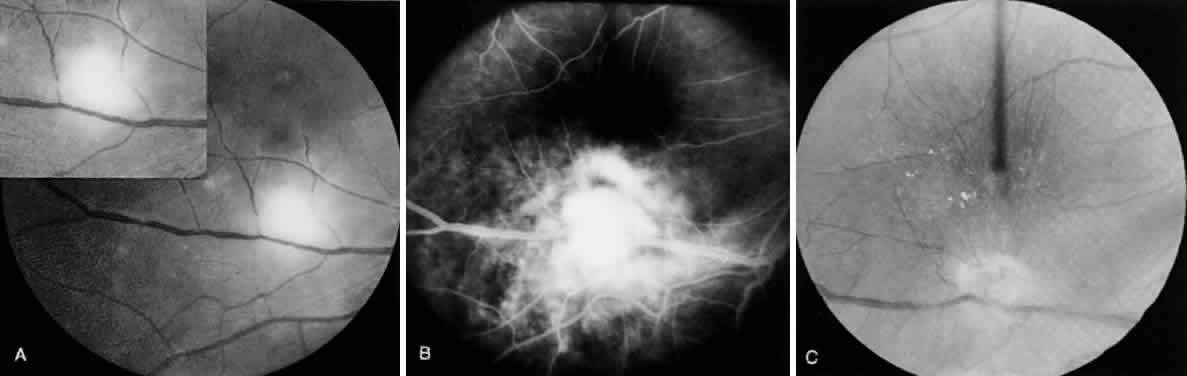

Bradyzoites are slowly metabolizing organisms found in cysts formed within the tissue of the infected host. The size of the Toxoplasma cyst varies, depending on the number of organisms that have multiplied within it. The cyst may reach more than 100 μm in diameter and may contain from 50 to 3000 organisms. The cyst wall is strongly argyrophilic and periodic acid-Schiff positive. It contains constituents that are derived from both the parasite and the host tissue. Constituent from the host tissue compose the outer part of the cyst, whereas those derived from the parasite are in the inner part of the cyst wall. Toxoplasmosis may be found in the inner layers of the retina after episodes of acute retinochoroiditis. The cyst may stay in the retinal tissue for years without showing any signs of invasiveness. Considering that the tissue cyst incorporates elements derived from the host into its outer wall, it is easily tolerated by the host, and no inflammatory reaction is seen around it (Fig. 2). It may remain for years in certain tissues, such as the eye or muscles, without provoking any inflammatory reactions. The bradyzoite inside the cyst derives its nutrition from the slow diffusion of substances through the cyst wall. The number of organisms increases within the cyst in the retina, and once the cyst wall breaks down by mechanical stretching, the bradyzoites escape, convert into tachyzoites, and invade contiguous cells. This process may lead to recurrence of retinitis. Certain immunologic mechanisms of the host may influence the organisms significantly. Immunosuppression coinciding with the rupture of the cyst and release of bradyzoites allows the organisms to become tachyzoites and proliferate in host tissue without restriction. The cyst of the Toxoplasma organism appears to be a defensive stage in its life cycle. The resistance of toxoplasmosis within chronically infected tissues of animals may lead to transmission of the disease by the ingestion of undercooked meat, including mutton, beef, pork, and chicken. Tissue cysts can develop within any organ and are commonly found in infected tissues of brain, eye, heart, skeletal muscles, and lymph nodes. Rupture of tissue cysts causes reactivation of the systemic toxoplasmosis in immune deficiency states, leading to dissemination of Toxoplasma organisms to other organs.

The definitive hosts of T. gondii are domestic and wild cats, whereas intermediate hosts encompass a wide variety of animals, including humans. In the definitive host, the parasite has both enteroepithelial and extraintestinal cycles. In the intermediate host, it persists in the extraintestinal cycle only. When oocysts from contaminated soil are ingested by animals, the oocyst wall is digested by the gastric enzymes, and the sporozoites are released. Similarly, when animals—including cats—ingest chronically infected tissues containing bradyzoites, the cyst wall is digested, and bradyzoites are released, leading to infection. Toxoplasma organisms then invade intestinal mucosal cells and initiate the infection (enteroepithelial cycle). In the intestinal mucosa, the organisms undergo asexual reproduction (endodyogeny, endopolygeny, splitting, schizogony) and sexual reproduction (gametogony cycles), culminating in the formation of zygotes, which develop into oocysts. The oocysts are shed in the feces of the definitive host. After oocyst excretion, sporulation occurs; the mature oocysts remain infectious in moist soil for a long time if not subjected to extreme climatic conditions.2 Freezing to -20°C, heating above 66°C, and desiccation are lethal to the cyst. Simultaneous with the enteroepithelial oocyst formation in cats, bradyzoites or sporozoites may invade and disseminate widely to all host tissue through the bloodstream or lymphatics, where they undergo an asexual cycle (extraintestinal cycle), particularly in muscle, heart, brain, lung, lymphoid tissue, retina, and central nervous system (CNS). The organism multiplies rapidly by endodyogeny in infected cells, forming pseudocysts containing tachyzoites. This usually leads to death and disruption of the cell, thereby liberating the tachyzoites, which enter contiguous cells in which they multiply, forming more pseudocysts. The rapidly proliferating tachyzoites are responsible for initial spread of the infection and tissue destruction (acute stage). In response to increased host immunity, tachyzoites transform into the slowly multiplying organisms, bradyzoites, which form true cysts in tissues (chronic stage). These can lie dormant in tissues throughout the life of the host but may cause reactivation of the clinical disease when the host's immunity is suppressed.6